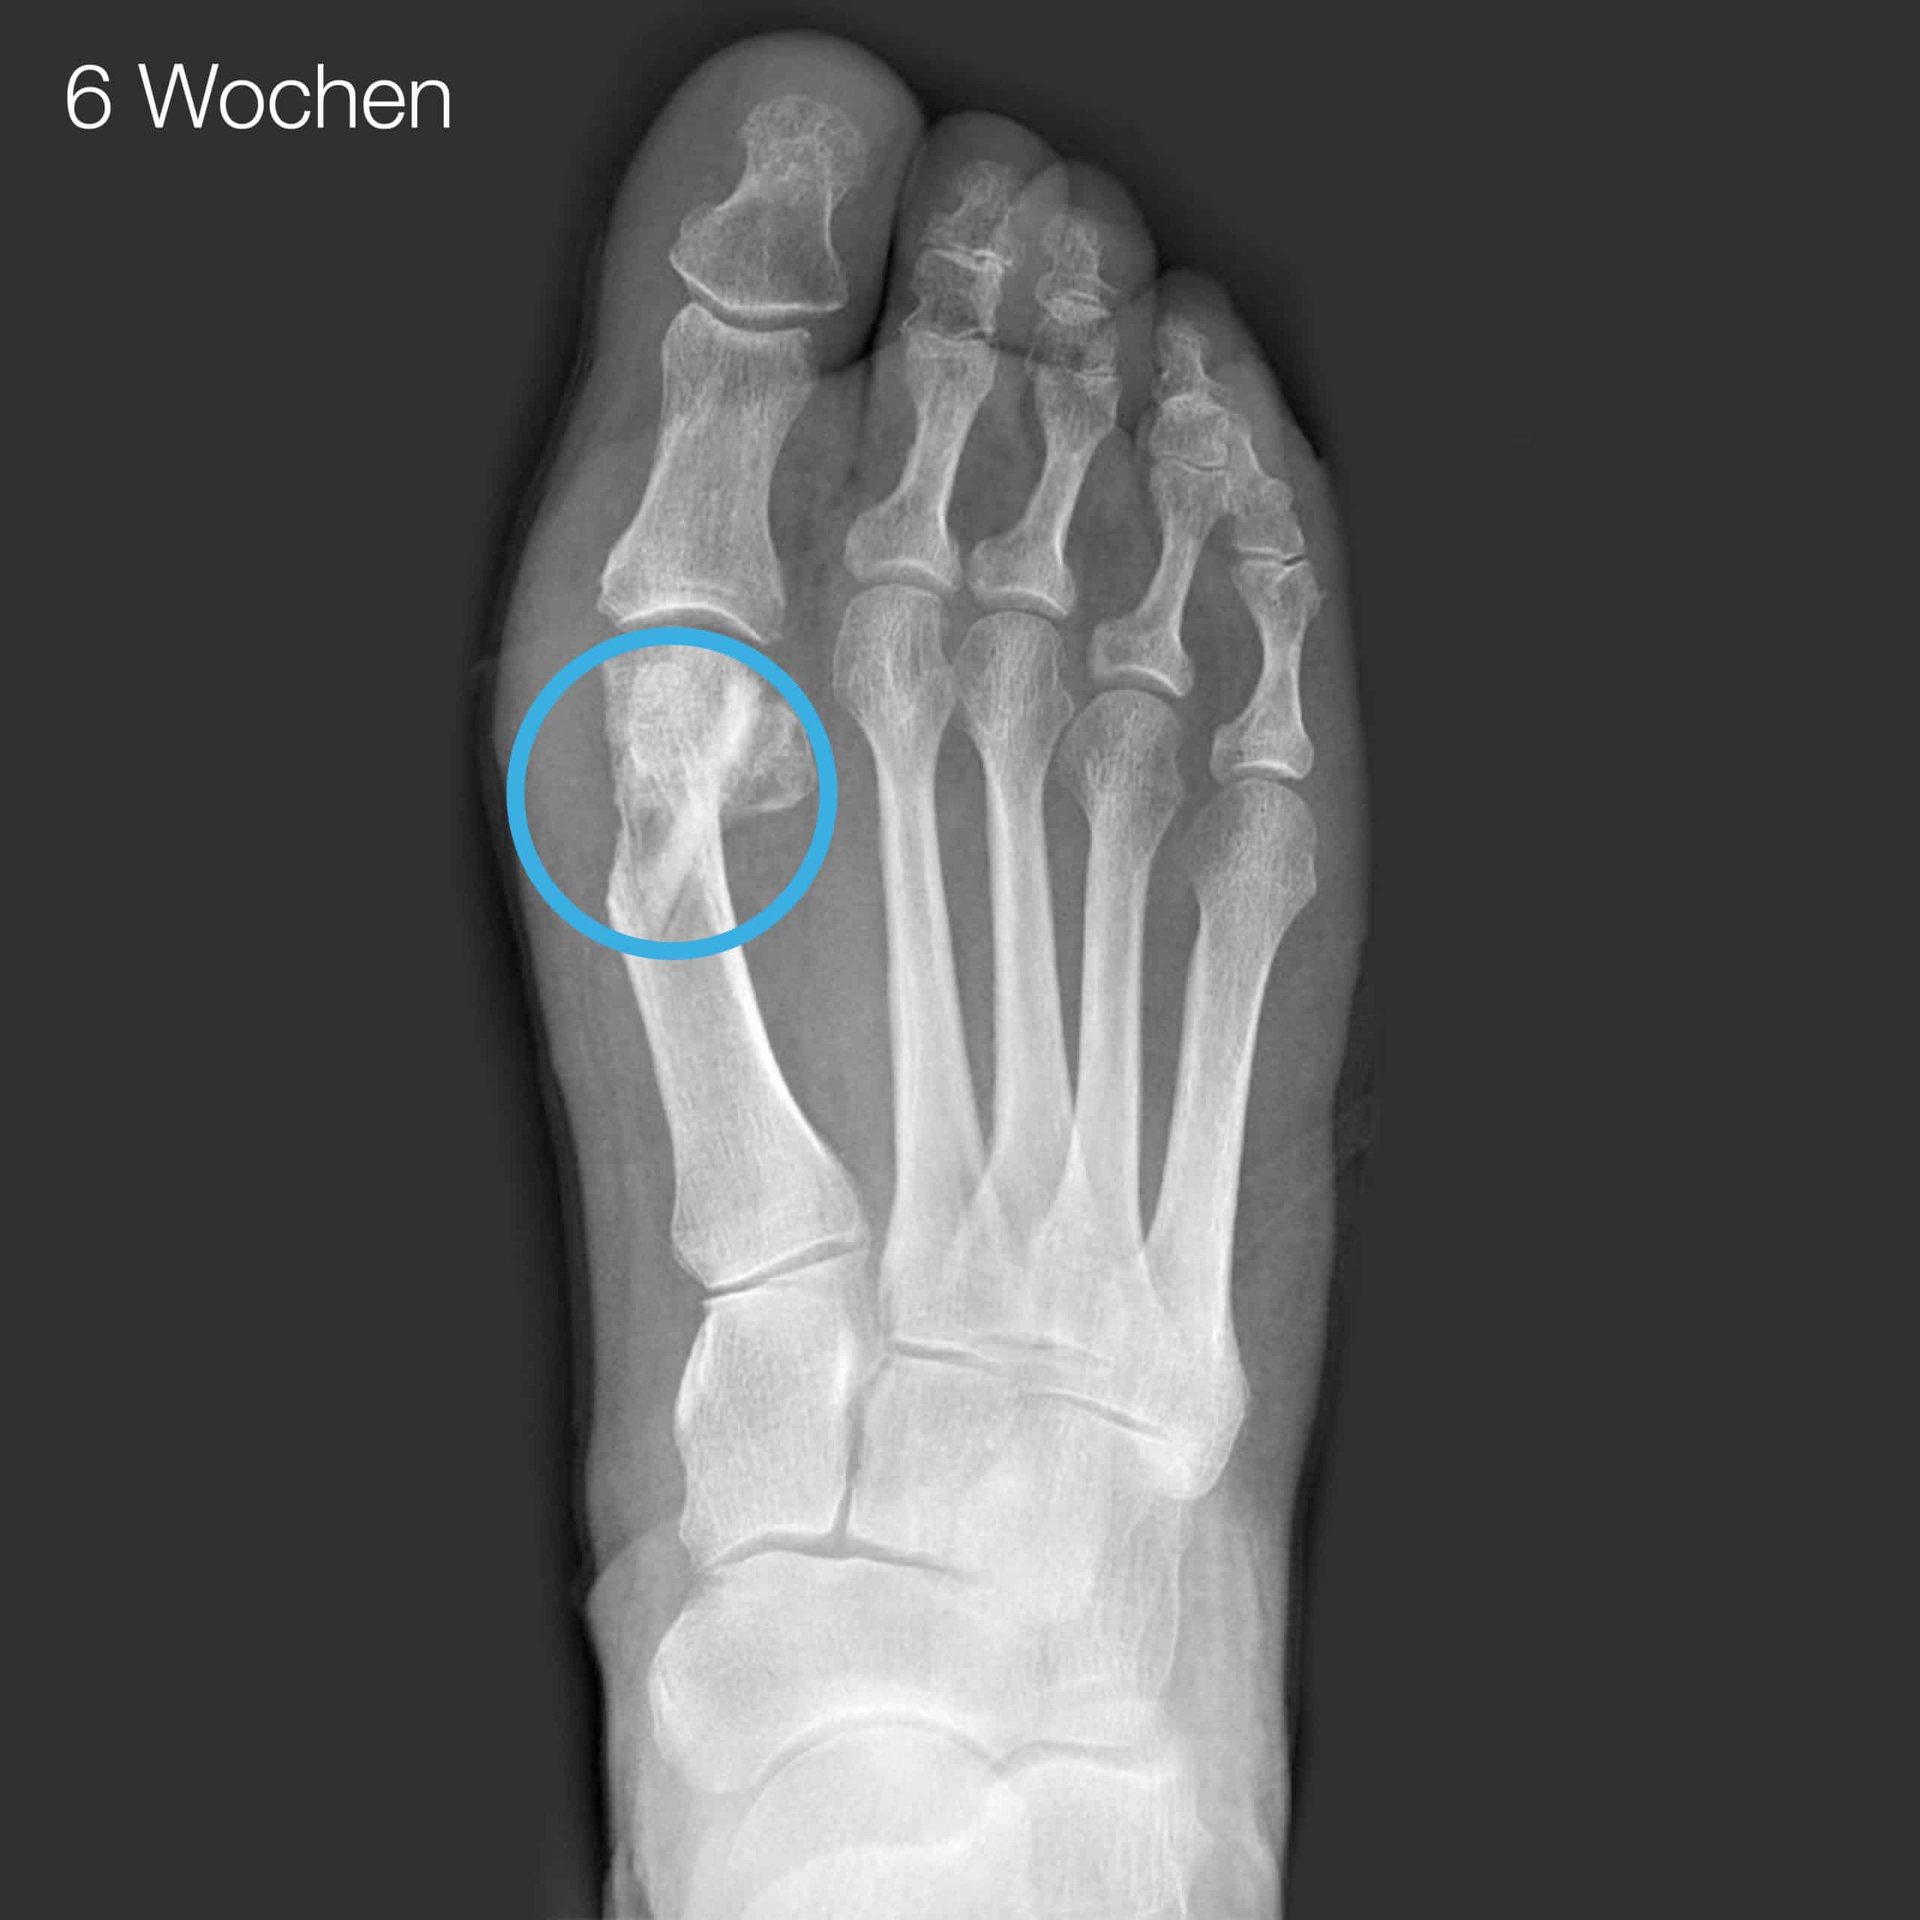

1 I. Brcic, K. Pastl, H. Plank, J. Igrec, J. E. Schanda, E. Pastl, M. Werner. Incorporation of an Allogenic Cortical Bone Graft Following Arthrodesis of the First Metatarsophalangeal Joint in a Patient with Hallux Rigidus Life (2021)